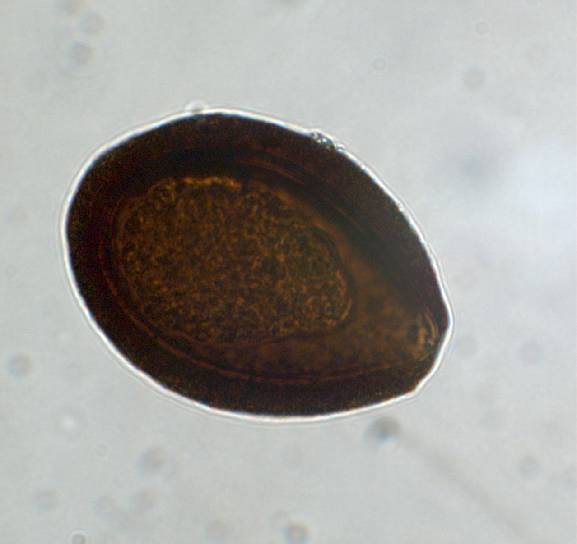

Eimeria leuckarti, oocyst

Relatively large, egg-shaped oocyst

with thick shell (approx. 80 x 55 µm)

and micropyle. Dark brown with

granular contents.